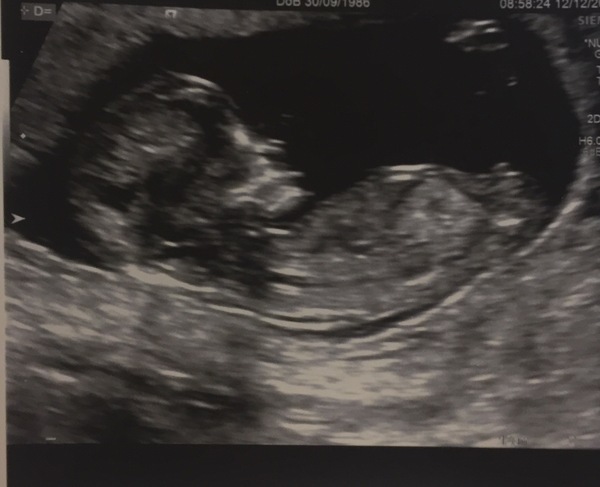

Great news re the scans yesterday. Good luck to anyone with theirs today.

12+6